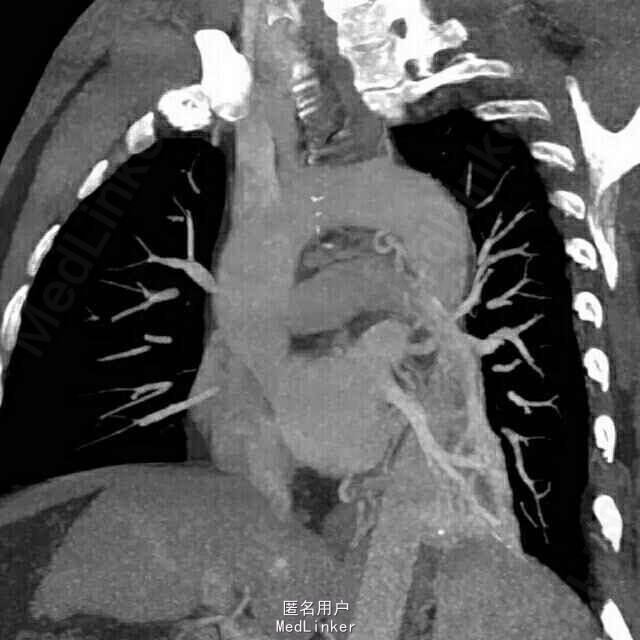

女,50岁。 间断咯血25年余,加重1月,行肺部增强CT。

患者胸部增强CT及血鬼重建影像学表现包括:边界清晰、病变有主动脉分支供血、病变静脉引流入肺静脉。

考虑影像学诊断为:肺隔离症

左肺下叶内前基底段脊柱旁可见斑片影,边界清晰,其内可见支气管气相,平扫密度尚均匀,增强后病变内强化不均匀,可见多发血管影,血管重建示病变由主动脉弓及降主动脉迂曲增粗的小分支供血,可见一直粗大静脉引流入左肺静脉。根据病变部位,供血动脉来源于体循环,静脉引流入肺静脉,此例为典型肺隔离症,已被术后病理所证实。 肺隔离症是一种先天性肺发育畸形,主要特征是部分胚胎肺组织与正常肺组织隔离,病变肺组织的动脉供应由体循环直接分出的动脉分支供应,静脉回流至肺静脉或体循环。尽管其表现多种多样,体动脉向肺组织供血为其最特征表现。常分为叶内型及叶外型2种,最常见为叶内型,多为体动脉单支血管供血,无单独胸膜包裹。叶外型有单独胸膜包裹,多位于膈肌下,由肺或体血管供血,血管较小,多伴有其他先天畸形。本例为叶内型,隔离的肺组织易反复发生感染,出现相关临床表现。 肺炎主要表现为肺实变或不张,常伴有病变周围斑片或淡片影,边界可不清晰,临床症状有助于诊断。 肺癌侵犯病变内及周围血管、支气管,造成支气管闭塞伴远端阻塞性炎症,肺门及纵隔常见肿大淋巴结。 支气管扩张伴感染时可见扩张的支气管,可为管状、串珠样或囊泡状,病变周围感染呈斑片影,边界欠清晰。